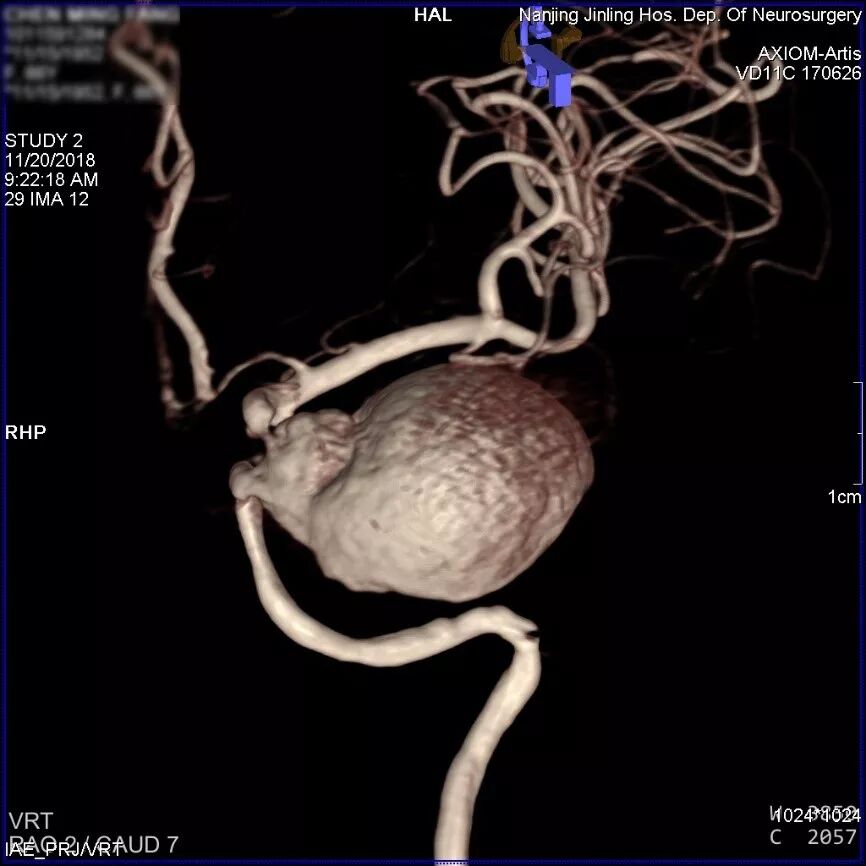

左侧颈内动脉海绵窦段巨大动脉瘤,余颅内血管未见明显异常。

患者取平卧位,气管插管全麻,右侧股动脉穿刺,置入6F 70cm长鞘至左侧颈总动脉,5F Navien中间导管在Marksman引导下超选至动脉瘤近端,行3D旋转造影显示:左侧颈内动脉海绵窦段大型血栓性动脉瘤。

显影部分动脉瘤大小约31.6*23.1mm,瘤颈宽6.4mm,载瘤动脉远端直径约为2.93mm,近端约为2.89mm。根据造影情况决定行血流导向装置置入术,选择Pipeline Flex 3.0mm*35mm。